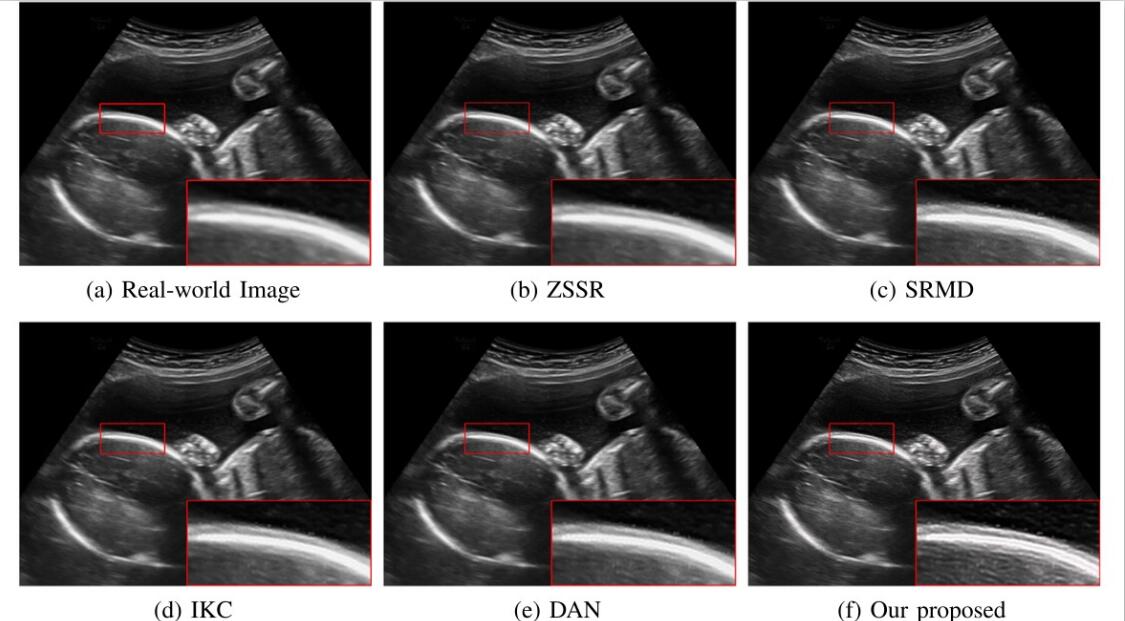

对于超声临床诊断而言,超声影像超分辨(ultrasound image super-resolution)可以提高超声成像质量,从而提高疾病诊断的准确性。但由于传感设备和传输介质的差异,实际场景中超声成像其退化模糊过程是未知且不可控的。为了解决未知退化场景超声医学影像准确超分辨的难题,团队提出了一种有效的基于退化模糊自估计且结合渐进残差学习和记忆提升机制的超声影像盲超分方法,初步实现了真实场景超声影像准确超分辨。相关研究成果发表在人工智能、计算机医学信息交叉领域一区TOP期刊《IEEE Journal of Biomedical and Health Informatics》(IF: 7.7)。ac米兰为论文第一完成单位,计算机学院刘恒教授、硕士生刘建勇分别为论文第一、第二作者。

(真实场景超声影像盲超分效果对比图)